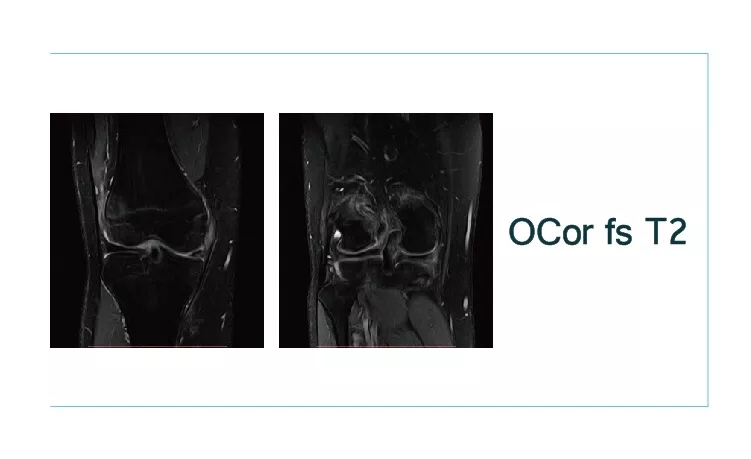

【朗润影像档案】20180914磁共振影像病例讨论结果